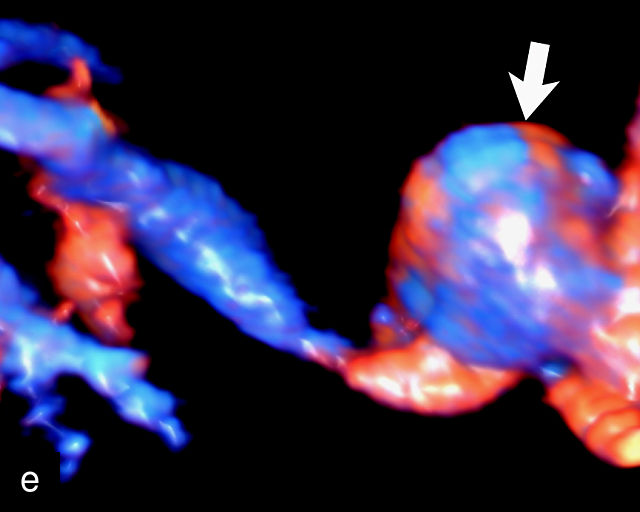

The typical sonographic appearance of a chorioangioma on grayscale ultrasound is a well-circumscribed mass arising from the fetal surface of the placenta, protruding into the amniotic cavity, and distinctly separate from the placenta (Figure 12; Video 7). These tumors are most commonly located near the umbilical cord insertion site on the placenta. Sonographically, they may appear hypoechoic or hyperechoic and are often heterogeneous, with possible calcifications, hemorrhage or infarction visible within the mass.9 The appearance of these masses may change over time.141 Color flow Doppler imaging typically reveals vascularity within the tumor, showing low-resistance vessels and arteriovenous shunts (Figure 12c–e; Video 7).9 These shunts are believed to contribute to fetal complications such as high-output cardiac failure, anemia and hydrops.141 Three-dimensional ultrasound may be helpful in assessment of the mass.146 Importantly, the differential diagnosis includes placental hemorrhage, and color flow Doppler is essential to assist in making the diagnosis.

12

Grayscale (a,b), color Doppler (c,e) and power Doppler (d) images of chorioangiomas, showing heterogeneous masses protruding from the placental surface.

7

(a–c) Color flow and power Doppler imaging of placental chorioangiomas.

When a chorioangioma is identified on prenatal ultrasound, close fetal surveillance is essential. Initial monitoring includes weekly ultrasound examinations to assess amniotic fluid volume and fetal cardiac function, as polyhydramnios and hydrops can develop rapidly. Polyhydramnios is the most common complication of chorioangioma, complicating between 14% and 28% of cases, and when severe, may lead to maternal discomfort, respiratory embarrassment and preterm labor.141,143,147,148 Fetal growth should be evaluated every 4 weeks. Maternal mirror syndrome, with severe pre-eclampsia has also been described.149,150

Management of complications related to chorioangioma may include interventions such as amnioreduction to manage severe polyhydramnios.149,151 More recently, a variety of fetal surgical procedures have been developed to treat these tumors, with varying degrees of success. Additional interventions include intrauterine fetal transfusion to correct anemia and various fetoscopic techniques to occlude tumor vessels, such as embolization with injection of vascular plugs, and radiofrequency or laser ablation of the feeding vessels.143,144,152,153,154,155,156,157